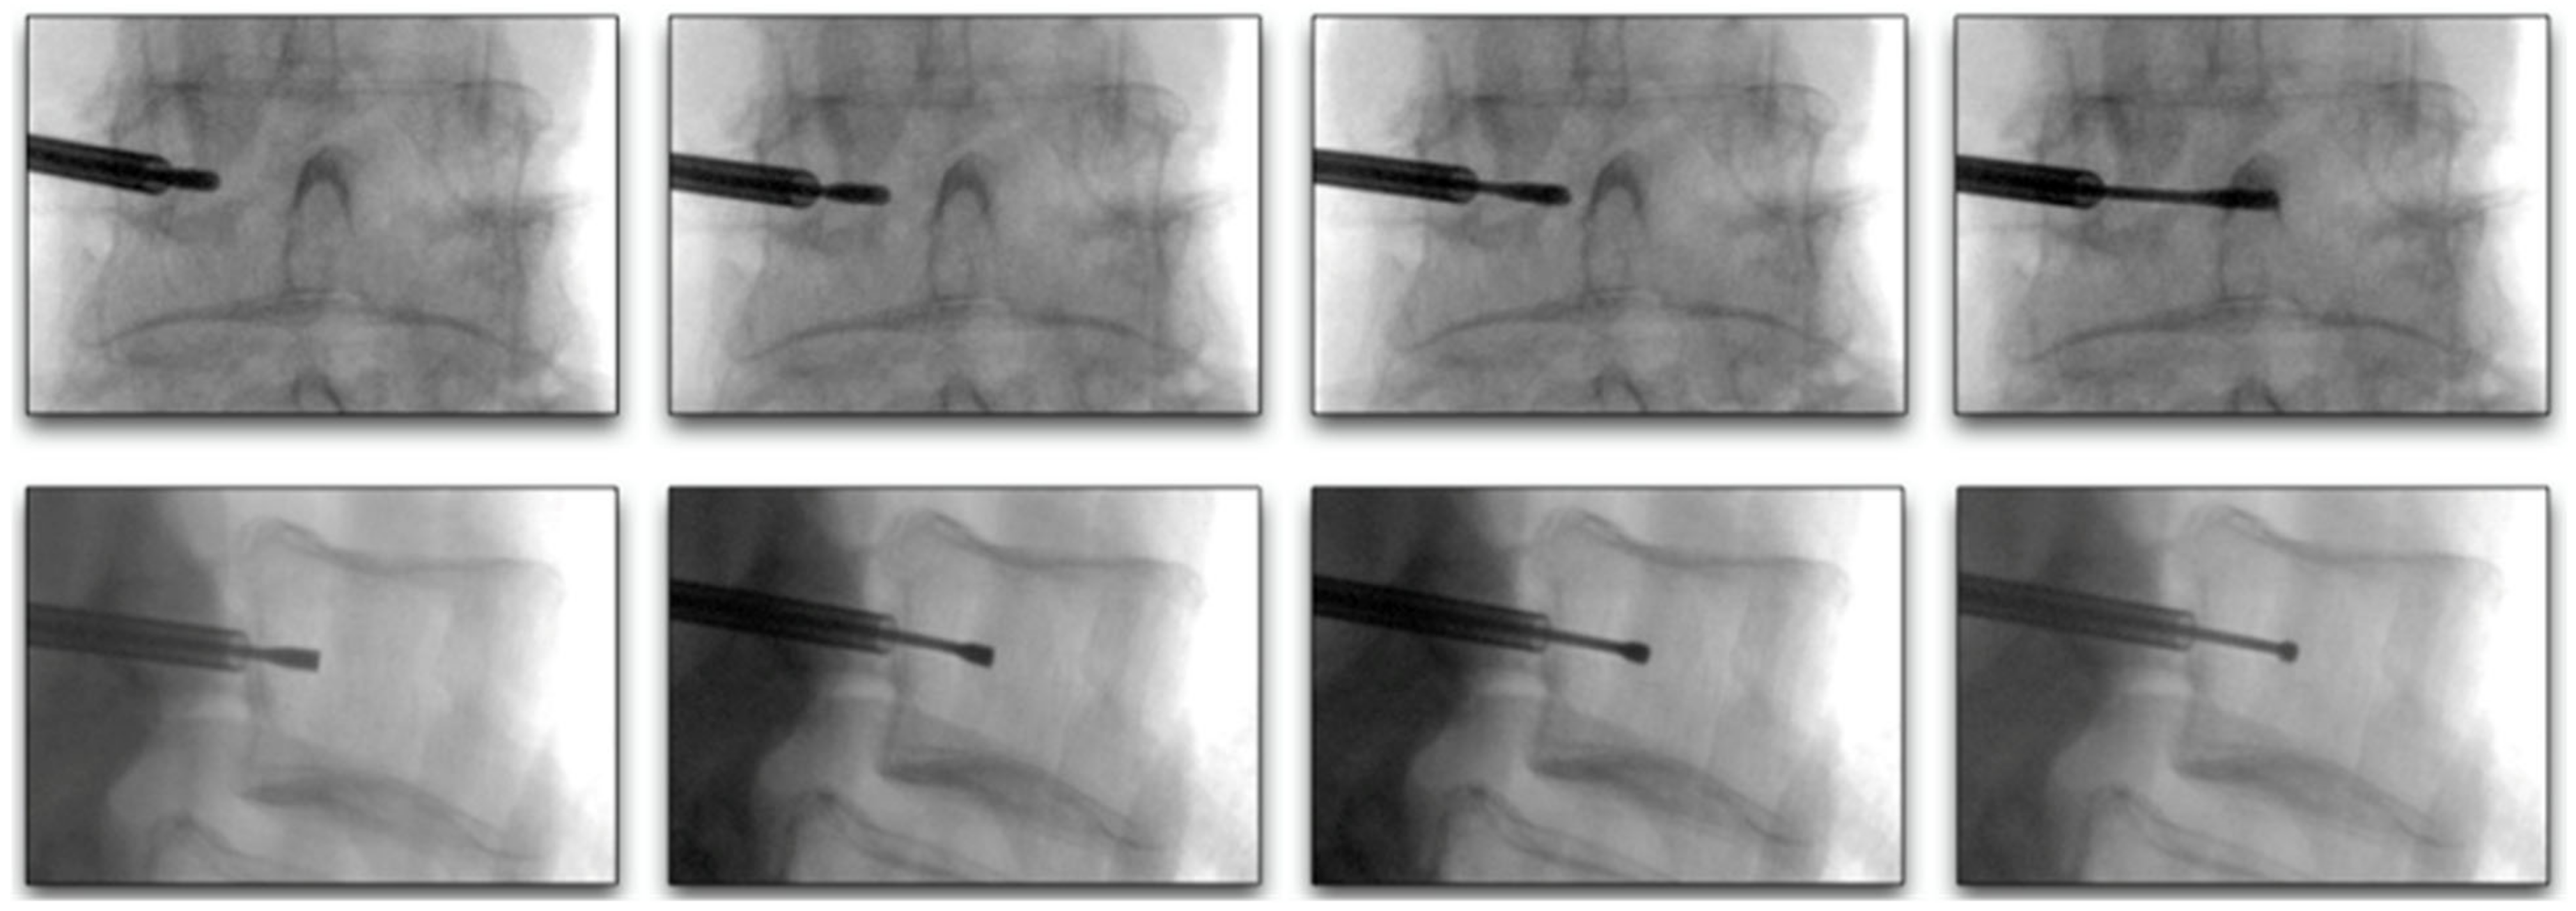

Figure 6.

Lateral and AP fluoroscopy views of curved stylet advancement towards the ideal location between the 25–40% midline, between the anterior and posterior vertebral walls.

Vertebrogenic pain from endplate disruption is an etiology of chronic LBP that presents clinically different from other sources. Historically, the etiology of axial lumbar spine pain has been attributed to many anatomical structures, such as intervertebral disc degeneration, spinal canal narrowing, zygapophyseal joint pain, spinal ligaments hypertrophy, muscles and nerve root inflammation, etc. However, due to limited success with interventions targeting these structures, a recent shift in the vertebral pain treatment paradigm towards vertebral endplates has emerged. The basivertebral nerve (BVN) carries nociceptive input from damaged vertebral endplates related to inflammatory cytokines, substance p, and calcitonin gene-related peptide (CGRP), histologically confirmed with protein gene product (PGP) 9.5 positive staining under microscopy [111,112]. The BVN is a branch of the sinuvertebral nerve that enters the vertebral body and travels posterior-to-anterior to a bifurcation point about 50% into the vertebral body and divides cranially and caudally towards the endplates [113,114]. Basivertebral nerve ablation (BVNA) is a minimally invasive surgical treatment of vertebral pain performed similarly to vertebral augmentation and lumbar radiofrequency ablation, in the sense that it uses a transpedicular approach to the BVN bifurcation and delivers a high-frequency ablative lesion to interrupt nociceptive signaling from injured vertebral endplates (Figure 6) [115,116]. Vertebral endplates are highly vascularized structures that are particularly susceptible to post-traumatic degeneration, fissuring, intraosseous edema, and inflammatory changes [111,112,117,118,119]. These vertebral endplate changes have a specific phenotypic marker on MRI that directly correlates to vertebrogenic pain, known as Modic changes (MCs) type 1, type 2, and type 3 (Figure 7). Type 1 MCs manifest as the decreased signal intensity of fibrovascular intraosseous bone marrow edema on T1-weighted MRI sequences and as hyperintense or increased signal intensity on T2-weighted MRI sequences. Type 2 MCs represent fatty bone marrow infiltration and typically show an increased signal intensity in both T1 and T2 MRI sequence images in contrast to type 3 MCs that have decreased intensity in both MRI sequences [120,121,122]. Although MCs are radiological findings, their presence has been reported in up to 43% of subjects with spinal pain and is highly associated with this subset etiology [118,119,123,124]. Vertebrogenic pain from endplate damage presents clinically different than other etiologies of chronic LBP with reported painful episodes of greater duration and frequency and with significant functional impairment and disability compared to other etiologies. Pain tends to be axial and progressive in nature, aggravated by sitting, standing and spinal flexion and without radicular symptoms, numbness, tingling or motor weakness. This subset population tends to respond poorly to conservative treatment, epidural steroid injections, facet joint blocks and spinal surgery [112,118,119,121,123,124,125,126,127,128,129,130,131].